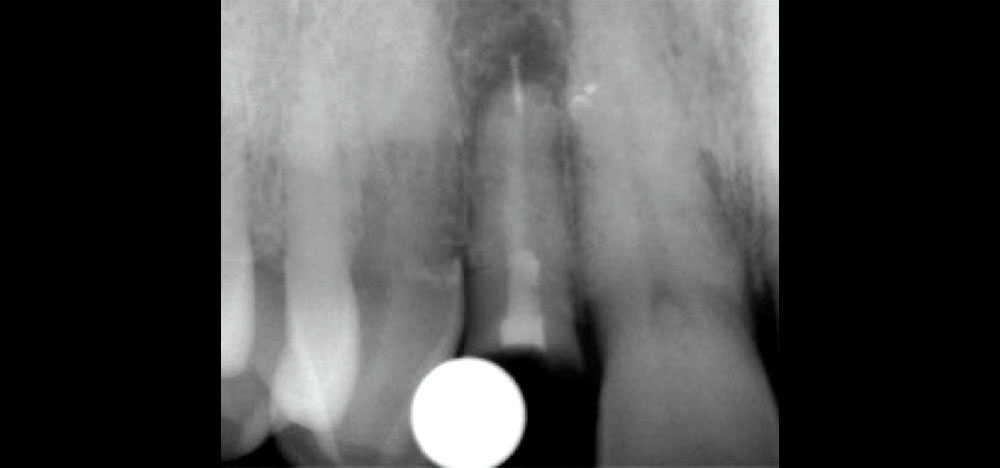

To achieve an optimal functional and esthetic outcome, the implant must be placed correctly with regard to trajectory, adjacent vital anatomy, and buccolingual, apicocoronal and mesial-distal positioning. Situating the implant so that the edges of the osteotomy are at least 2 mm from the buccal and lingual cortical plates, 2 mm from adjacent roots, 2 mm from vital structures, and 2–3 mm below the crest of tissue will keep the implant within the envelope of acceptability. The implant trajectory should emerge lingual to the incisal edge of the planned restoration, which allows for a screw-retained crown.

This case is an example of an ideal clinical situation for dentists who are new to placing implants in the esthetic zone. The patient requested treatment for a fractured upper lateral incisor. After extraction, grafting and healing, ample bone and soft tissue were present, and an implant was placed in optimal position for an esthetic result. The screw-retained restoration predictably restored form and function, illustrating the beautiful results that can be achieved by observing simple surgical and prosthetic guidelines.